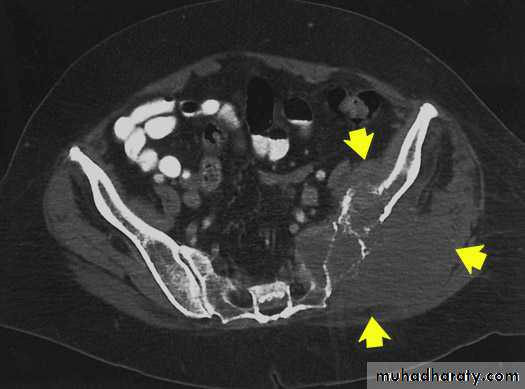

IV. computed tomography in bone disease (CT scan ) :

1.Demonestrating abnormality in the pelvis and spine2.Demonstrating the extent & characterization of bone tumour in selected cases to complement MRI

3.As gide of bone biopsy